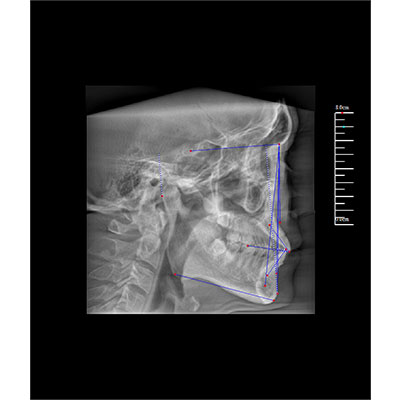

該款牙科CBCT產(chǎn)品采用動(dòng)態(tài)平板探測(cè)器,獲得三維圖像的同時(shí)還具有數(shù)字化全景功能,廣泛應(yīng)用于口腔頜面外科、正畸科、正頜外科、種植科、牙體科、顳下頜關(guān)節(jié)科等術(shù)前術(shù)后。

專有三維重建算法,可提供任意位置高清斷層影像。

可同時(shí)觀察軸向面、冠狀面和矢狀面圖像,方便臨床診斷。